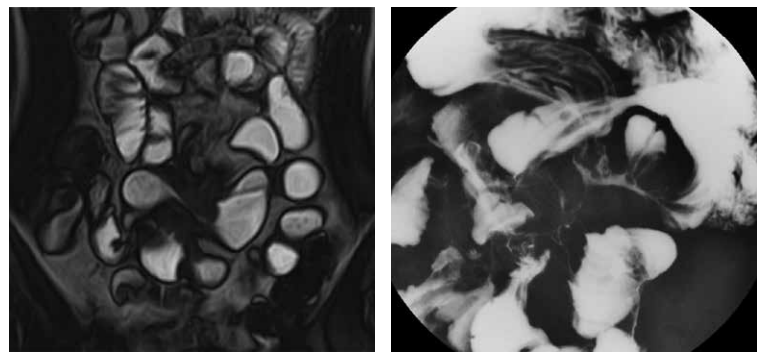

MRエンテログラフィー 3

腸管腸管ろう(小腸造影検査との比較)を認める。